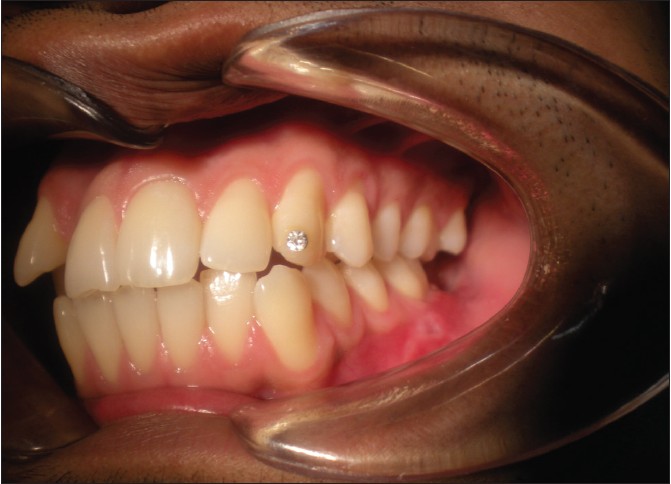

A 24-year-old male reported to the Department of Oral and Maxillofacial surgery in Mayya Multispecialty Hospital, Bangalore, India, complaining of asymptomatic facial swelling of 1 year. An intraoral clinical examination revealed a non-tender bilaterally palpable swelling. The swelling extended from the first premolar to third molar region on the right, and from the first premolar region to the retromolar trigone on the left [Figure 1] and [Figure 2]. The swelling obliterated the buccal vestibule bilaterally and there was associated mobility of the first and second molars on both sides of mandible. The overlying mucosa appeared normal in color, non-tender, hard in consistency, and smooth on palpation. The third molars were unerupted in all the four quadrants. There was no history of paresthesia in lower lip region. All the sensations were found to be normal in lower lip area on clinical evaluation. Vitality was found to be present in first and second molars, premolars, and anterior teeth after thermal stimulation test using hot gutta percha application on teeth. | Figure 1: Preoperative clinical photographs showing intraoral swellings in the retromolar area on right side

Click here to view |

| Figure 2: Preoperative clinical photographs showing intraoral swellings in the retromolar area on left side